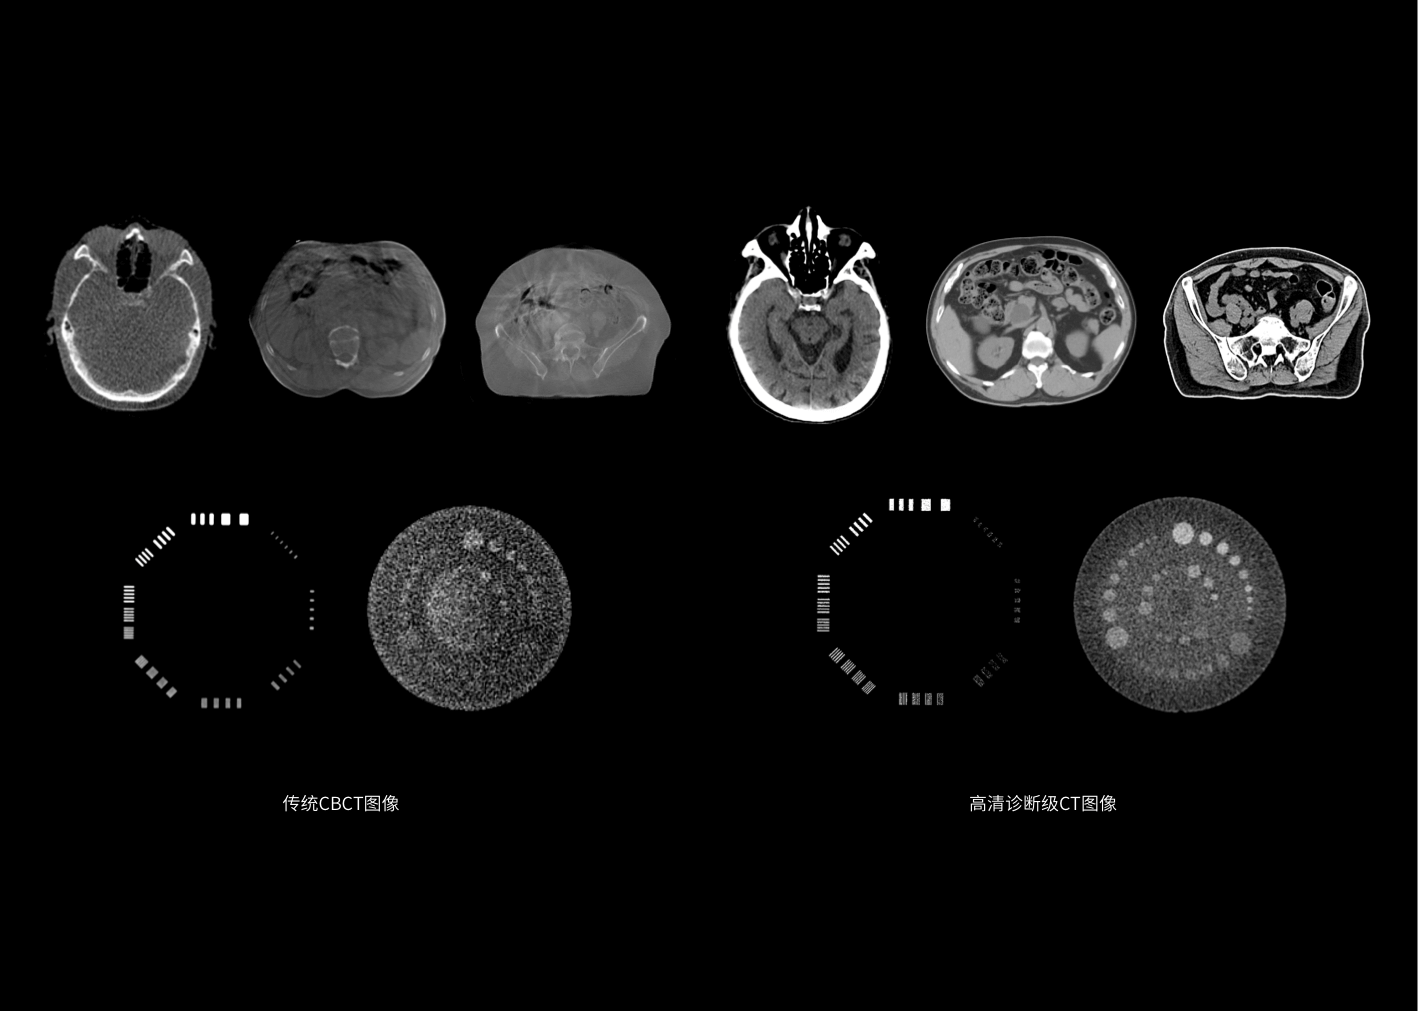

CT-IGRT高清图像引导

肿瘤形态高清监测

诊断级高清CT助力监测肿瘤变化,及时调整治疗方案,护航各分次放疗精确实施。